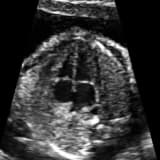

Çocuk kardiyoloji bölümünde yapılacak olan muayene ve asıl olarak da ekokardiyografi yani kalp ultrasonu ile bu üfürüm sesine neden olabilecek hastalıklar saptanır ve bazen ağır bazen hafif kalp hastalığı saptanır ve ona göre yapılacaklar belirlenir. Bazen de herhangi bir hastalık saptanmaz ve aileye gözünüz aydın kalbinde problem yok, sizin çocukta masum üfürüm dediğimiz ses var, bunun da bir önemi yok der göndeririz.